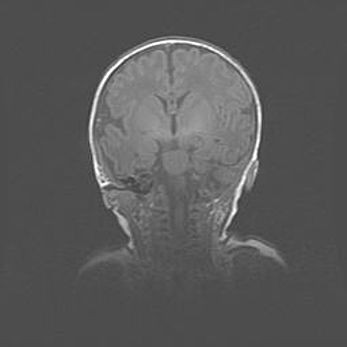

Множественные кисты обоих полушарий головного мозга, наибольшая из них в правой затылочной области. Ассиметричная атрофическая гидроцефалия.

Возраст: 7 месяцев

Вес: 5660 г

Пол: мужской

Окружность головы: 41,5 см

Срок гестации: 28-29 недель

Кисты головного мозга развиваются в результате многоочаговых некрозов вещества мозга и возникают вследствие перенесенной перинатальной инфекции, менингитов, энцефалитов, асфиксии, родовой травмы, расстройств мозгового кровообращения различного генеза. Образованию кист в веществе головного мозга плодов и новорожденных способствуют такие факторы, как высокое содержание в нем воды, недостаточная (или отсутствие) миелинизация и слабая астроглиальная реакция на повреждение.

Кисты могут сочетаться с гидроцефалией и другими поражениями головного мозга.